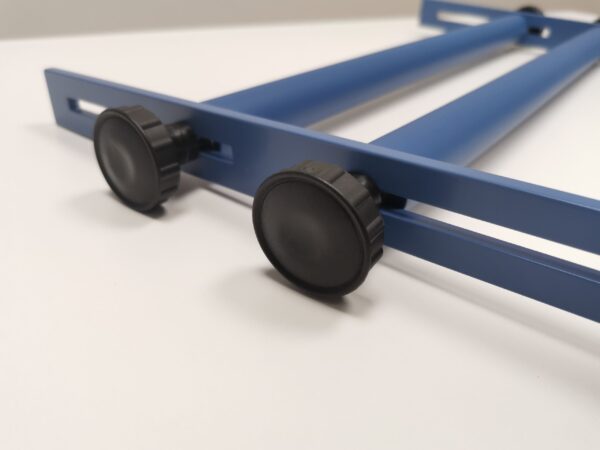

Narzędzie wspomagające ocenę luźności stawów biodrowych podczas badania ortopedycznego. Dystraktor wykorzystywany jest podczas diagnostyki dysplazji stawów biodrowych.

Urządzenie jest regulowane, w pełni kompatybilne z większością psich i kocich pacjentów. Regulacja rozstawu wałków od 6,5 do 28 cm.

| Waga | 1,1 kg |

| Wymiary | 50 × 30 × 3 cm |